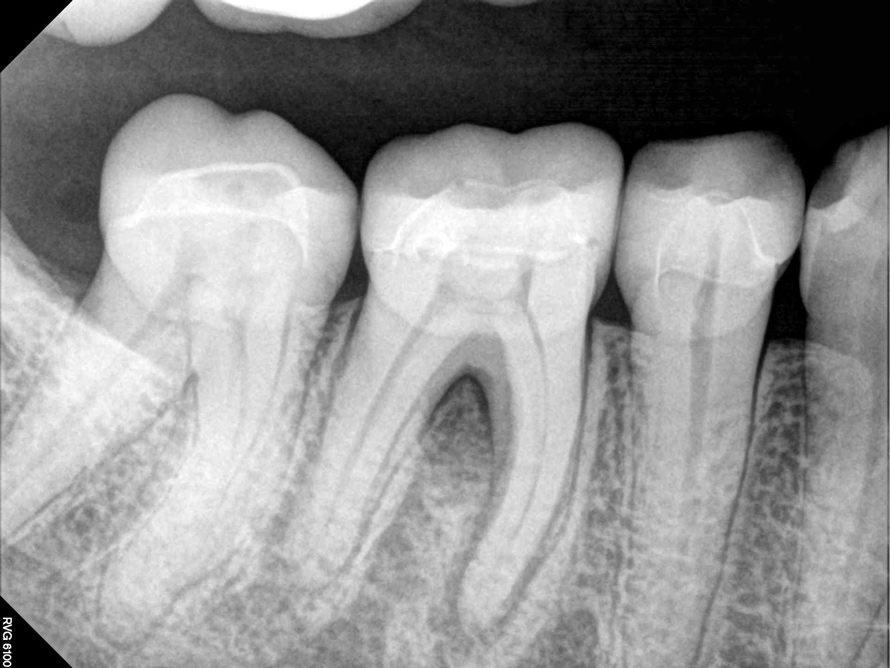

Fig 2. Tooth No. 14 was treated with silver points. In Figure 2, tooth No. 18 with mesial canals treated with Sargenti paste. The hallmark radiographic appearance of this technique is the light radiopacity within the canal system, as in Figure 3.

Figure 2

Fig 3. Tooth No. 14 was treated with silver points. In Figure 2, tooth No. 18 with mesial canals treated with Sargenti paste. The hallmark radiographic appearance of this technique is the light radiopacity within the canal system, as in Figure 3.

Figure 3